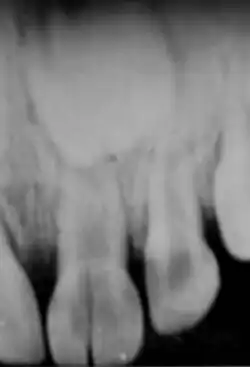

Kronenfraktur 11 und 21 ohne Pulpaeröffnung; 11 ist bereits mit einer Füllung rekonstruiert worden

Bei den Zahnfrakturen unterscheidet man je nach Lokalisation zwischen Kronenfraktur (an der klinischen Krone des Zahnes) und Wurzelfraktur (an der Zahnwurzel). Nach dem Verlauf der Frakturlinien wird zwischen Quer-, Längs- und Schrägfraktur unterschieden.

Kronenfraktur

• Dentin-Frakturen (im Zahnbein) – genauer: Schmelz-Dentin-Fraktur, da eine Dentinfraktur nur bei gleichzeitiger Fraktur des Zahnschmelzes vorliegen kann – mit oder ohne Pulpenbeteiligung

• Dentin-Frakturen ohne Eröffnung der Zahnpulpa (Zahnmark, „Zahnnerv“)

Zahnschmelz-Frakturen an Schneidezähnen können sehr gut mit einer Komposit-Füllung (Kunststofffüllung, Adhäsivtechnik) versorgt werden. Bei sehr kleinen Zahnschmelz-Frakturen ist oft keine Füllung erforderlich, es reicht dann ein mehr oder weniger leichtes Verschleifen und Abrunden der scharfen Bruchränder, auch zur ästhetischen Korrektur. Schließlich nutzt sich die Schneidkante im Laufe weniger Jahre auch auf natürlichem Wege beim Kauen leicht ab.

Bei Dentin-Frakturen ohne Pulpaeröffnung (ohne Pulpabeteiligung) wird eine Komposit-Füllung gelegt oder die Zahnform mittels einer Zahnkrone wiederhergestellt. Das freigelegte Dentin ist gelblicher, als der Zahnschmelz und schmerzsensibel. Es sollte mit einer Füllung abgedeckt werden, da es sich infizieren kann. Bei größeren Dentinfrakturen, die schon dicht an die Pulpa reichen, ist vor der Füllungs- oder Kronentherapie eine indirekte Überkappung der Pulpa erforderlich (meist mit Calciumhydroxid).